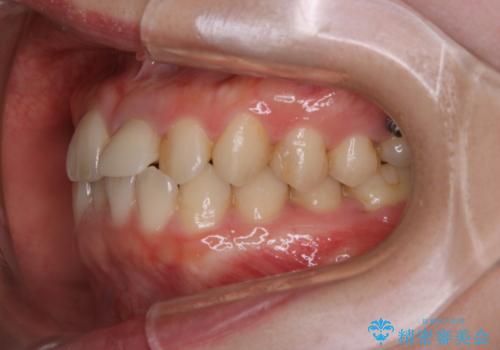

インビザラインのアタッチメントをつける前にPMTC

- インビザラインでの矯正治療中で、アタッチメントの設定前にきれな状態にしたいとのことでした。PMTC30分コースを行いました。

マウスピース矯正インビザライン治療では、歯の表面にアタッチメントという突起を設定します。(アタッチメントは歯の動きを効率的に移動するためのものです)

アタッチメントの設定時に、プラークや歯石・着色がついていると精密に付かないことや、外れやすくなることがあります。

PMTCを行い、専門的な機械でしっかりと汚れを除去してからアタッチメントの設定をすることがおススメです。